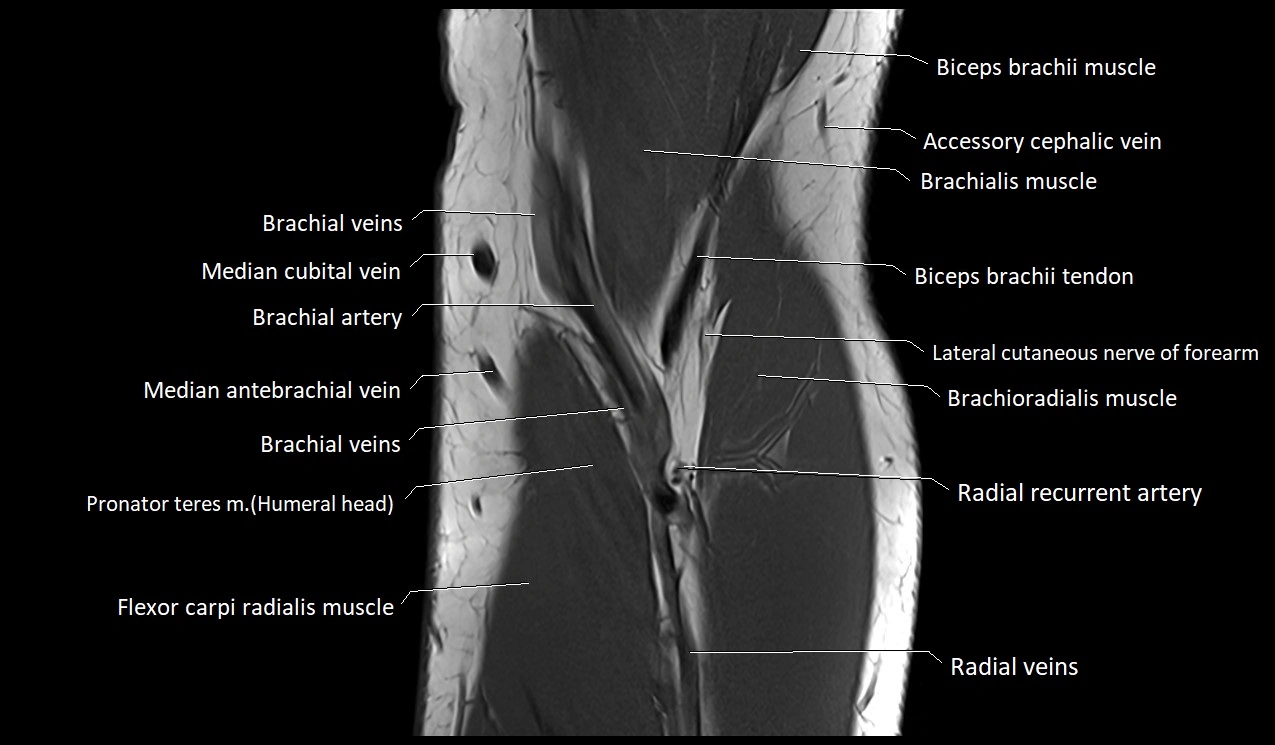

MRI image

image